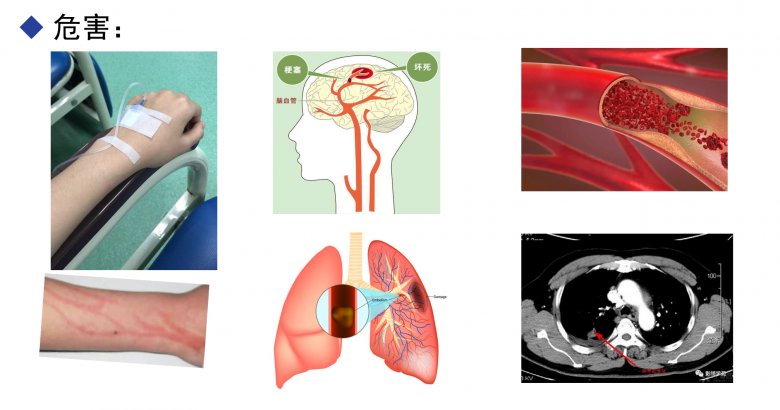

注射劑中的不溶性微粒是指藥品在生產或使用過程中經由各種途徑產生或混入的微粒性雜質,粒徑在1~50 μm、肉眼不可見,但因其可隨血液流動卻不能被代謝而可能對人體造成難以發現和潛在的嚴重危害。20世紀30年代起研究人員開始認識到不溶性微粒的危害,并于60、70年代間對此開展了大量的實驗及臨床研究,隨后不溶性微粒控制被納入注射劑質量標準,且其檢測方法得到不斷改進。現在,有關注射劑中不溶性微粒可能對人體造成危害的觀念已為臨床廣泛接受,過敏反應、靜脈炎、血管栓塞、微循環堵塞、動脈硬化、熱原反應、肉芽腫、肺栓塞等多種與不溶性微粒有關的不良反應都會引起醫護人員的重視。

不溶性微粒的傷害

《中國藥典2020版》對注射劑中不溶性微粒的控制要求僅限于粒徑≥10和25 μm的微粒數,對粒徑<10μm的卻沒有具體要求,實際上,人體最小的毛細血管內徑僅有4~7 μm,嬰、幼兒的毛細血管更細,只有粒徑在2 μm以下的微粒才可能通過腎交換被排出體外,而粒徑為2~10 μm的微粒無法被排出。微粒進入體內造成危害的部位一般多在肺、腦、腎、眼等處,較大的微粒會直接造成局部循環障礙、引起血管栓塞或導致肉芽腫,且有短期內可見的特點,而粒徑為2~10 μm的微粒則可能造成潛伏性的更大危害。